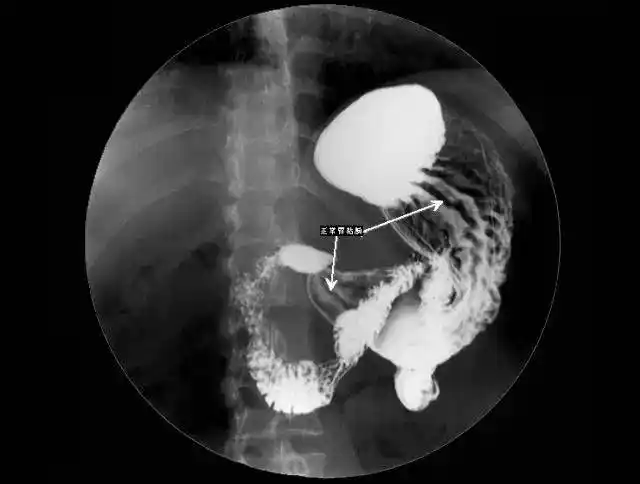

请医生帮我分析下,这个应该是什么病,胃溃疡或者胃癌?

胃溃疡患者就诊时,医生通常都是怎么诊断的

胃溃疡